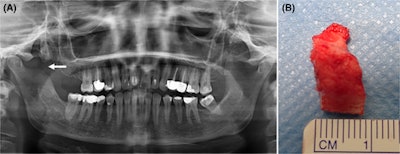

The (A) panoramic x-ray after surgical treatment shows partial resection of the lesion and the coronoid process (arrow). A (B) clinical image of the resected lesion. Images courtesy of Pedersen et al. Licensed by CC BY 4.0.

Following the dental procedure, the woman experienced persistent limited mouth opening. Eventually, she made a full recovery after undergoing a coronectomy and engaging in physical therapy and regular jaw exercises, according to a report published in Clinical Case Reports.